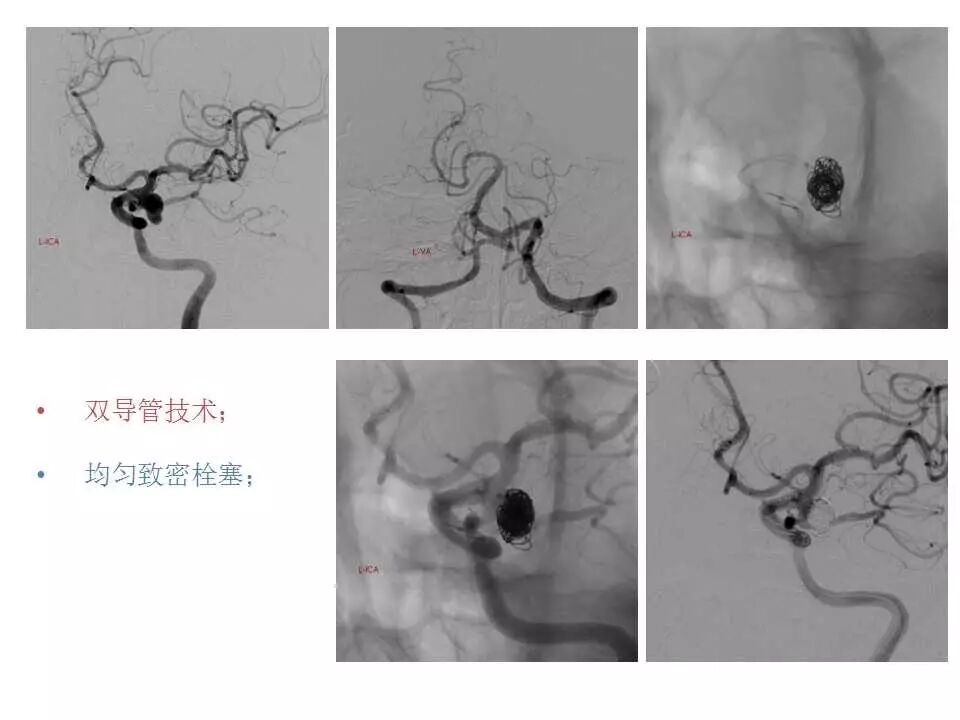

今天为大家分享的是“强生医疗CNV-神经介入专栏”第十五期,由首都医科大学宣武医院何川教授带来的“颅内动脉瘤介入治疗”精彩讲课视频及PPT,欢迎观看、阅读。文章仅代表作者个人观点,如有不同见解,欢迎同道斧正!

何川 ,首都医科大学宣武医院副主任医师,中国医师协会神经介入专业委员会常务委员,长期从事脑血管病和脊髓血管病的手术及介入治疗和相关研究工作。首都医科大学神经外科博士,师从于中国神经介入开创人凌锋教授;日本东北大学医院脑血管病治疗科博士后,师从于日本国脑血管病血管内治疗的开创者高桥教授。